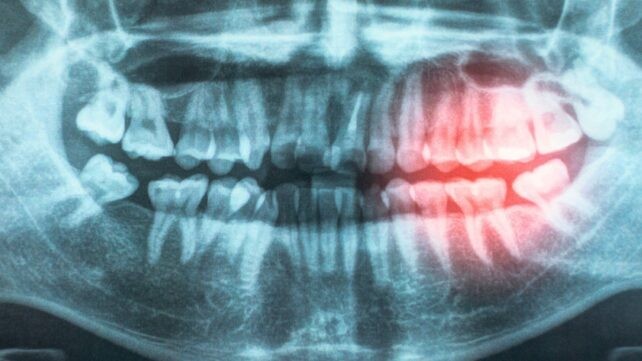

A review by the American Heart Association Cardiovascular Disease Prevention Committee strengthens the case that keeping our gums healthy helps protect against heart disease. Informed by a decade's worth of literature that includes genetics investigations, clinical trials, and lab tests, their report updates their 2012 scientific statement, providing even stronger evidence that heart problems triggered by clogged arteries (atherosclerotic cardiovascular disease, or ASCVD) are closely associated with periodontal disease. As part of their review, the researchers explored possible reasons for the association, including the likelihood that bacteria enter the body through exposed and damaged gums, contributing to chronic inflammation. Related: Study Links Gum Disease With White Matter Damage in The Brain

"Your mouth and your heart are connected," says pediatric cardiologist Andrew Tran. "Gum disease and poor oral hygiene can allow bacteria to enter the bloodstream, causing inflammation that may damage blood vessels and increase the risk of heart disease." One major challenge for those studying this link is that so many risk factors – from smoking to aging to obesity – increase the chances of both gum disease and ASCVD. Yet new evidence has continued to emerge suggesting that there is an independent association between the two conditions. ASCVD remains the number one cause of death globally, and if improving oral hygiene could potentially be one way of stopping it from happening, that's worth investigating. Some of the studies analyzed included details on subjects going back to childhood, finding that looking after your teeth at a young age could lower the risk of heart problems later in life. "There is strong evidence that treating periodontal disease improves intermediate outcome measures, such as blood pressure, high-density lipoprotein cholesterol level, and inflammatory markers," write the researchers in their published paper. "This is an important finding because these outcome measures are known to increase future cardiovascular risk and provide a possible link between periodontal disease and ASCVD."